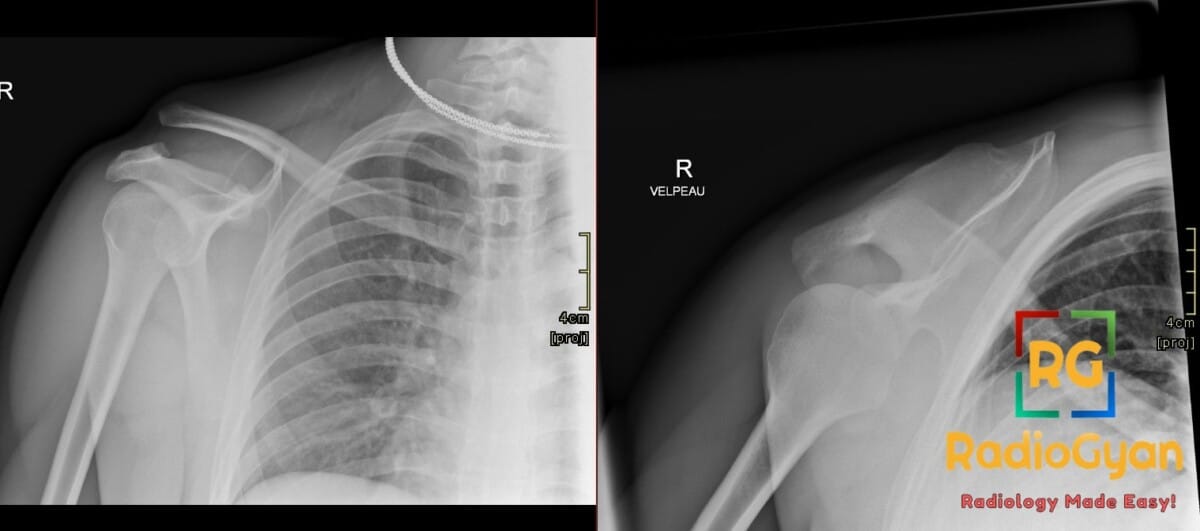

25 yr male presenting with localized shoulder pain and superior clavicular deformity following a fall during a rugby match.

Diagnosis: Right acromioclavicular joint injury

- Radiograph: Findings include AC joint widening (>7 mm), increased CC distance, and superior displacement of the distal clavicle; weight-bearing stress views can help differentiate stable Type II from unstable Type III injuries.

- Signs: Step deformity refers to the vertical misalignment between the inferior borders of the acromion and distal clavicle on an AP view; Zanca sign utilizes a specific radiographic angle to highlight joint space widening.